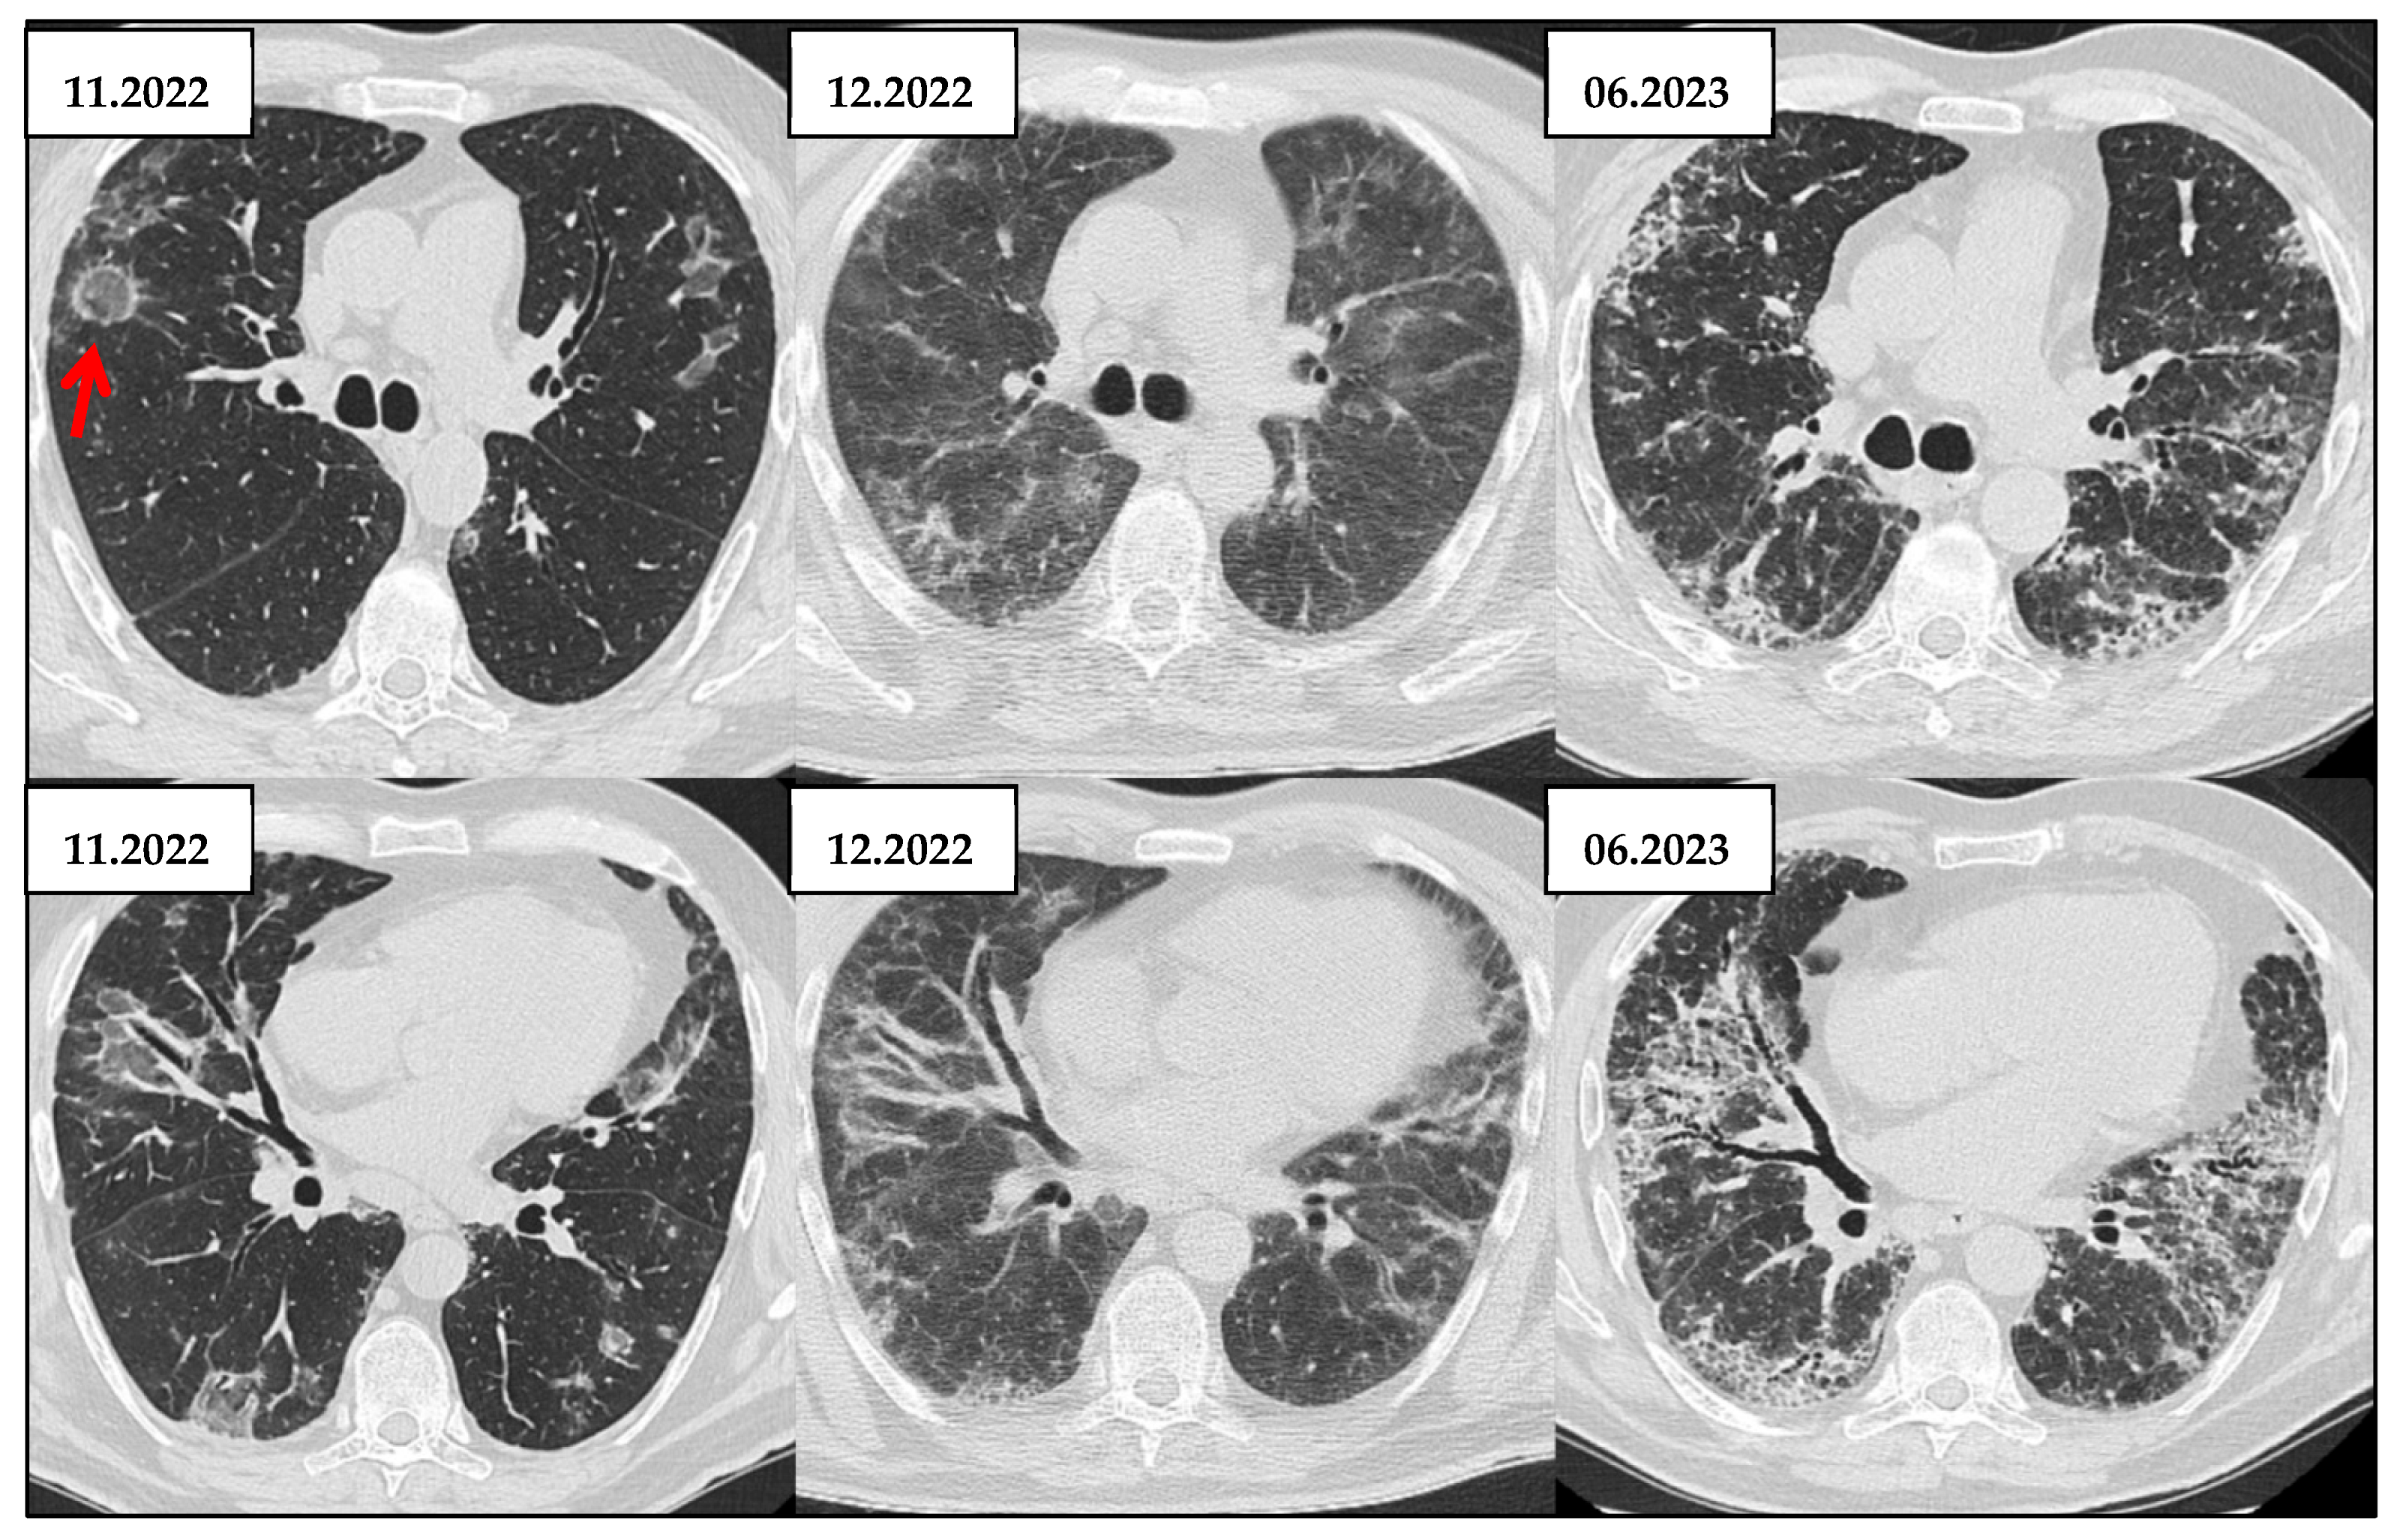

3.5. Role of HRCT in Longitudinal Assessment of CTD-ILD

| HRCT Patterns | - UIP is the most common pattern (~40–60%)—strong negative prognostic marker - NSIP (~15–25%) - OP and mixed types less frequent. (<20%)  | [43] |

- Lee, J.S.; Kim, G.-H.J.; Ha, Y.-J.; Kang, E.H.; Lee, Y.J.; Goldin, J.G.; Lee, E.Y. The extent and diverse trajectories of longitudinal changes in rheumatoid arthritis interstitial lung diseases using quantitative hrct scores. J. Clin. Med. 2021, 10, 3812. [Google Scholar] [CrossRef]